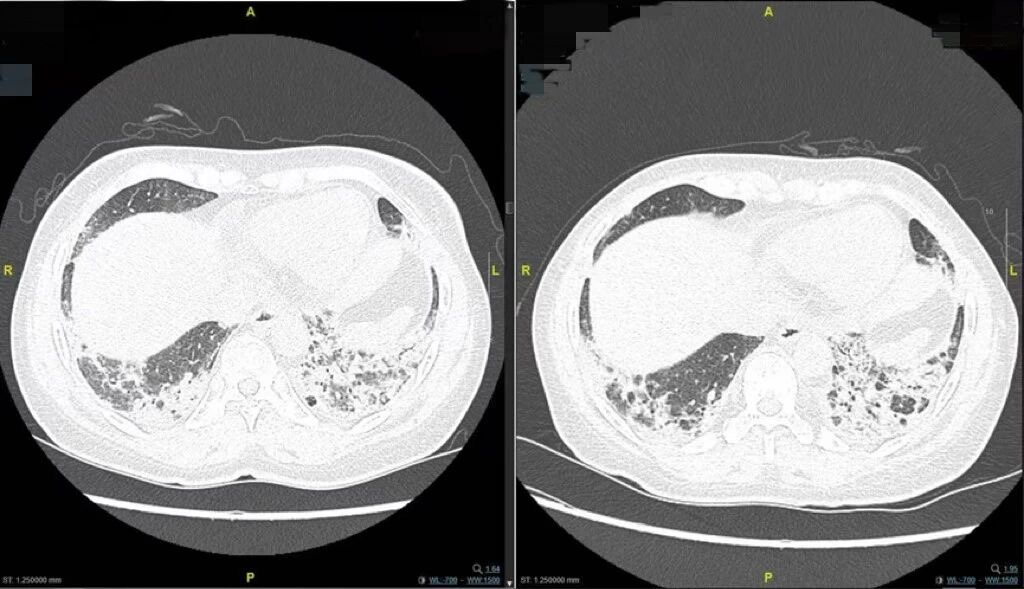

一个月前,袁女士开始出现全身水肿与关节肿痛,双手皮肤紧绷如同戴了一层厚手套。更让她担心的是,一活动就感到胸闷气促,生活质量一落千丈。在当地医院检查未果后,她来到南京明基医院。胸部CT检查示双肺已出现广泛的间质性病变。同时,专科查体发现了特征性的“技工手”,血液检查更揪出了罕见的“抗Jo-1抗体”强阳性。谜底终于揭开——抗合成酶综合征,这是一种会攻击肺部、肌肉、关节等多系统的自身免疫病。

经过系统性的强化治疗,袁女士的病情很快出现了转机。她感到最明显的改善是呼吸变得轻松了。这一转变在客观检查上也得到了印证。治疗后的复查胸部CT显示,其双肺的间质性病变较前明显吸收好转,肺里的“蜘蛛网”正在消散。同时,听诊时那双肺标志性的、提示肺纤维化的Velcro啰音(爆裂音)也显著减轻。这一切都标志着她的肺部炎症得到了有效控制,肺功能正在稳步恢复。